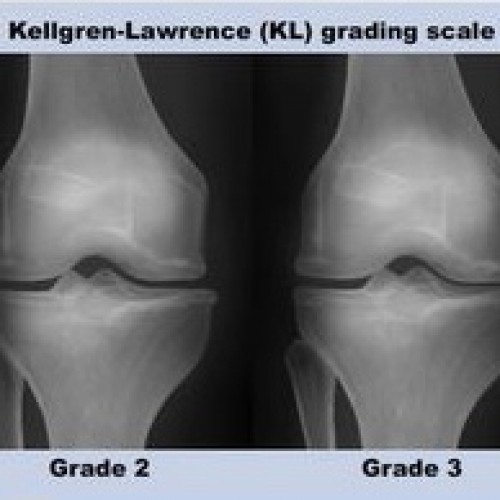

ARTROSE DO JOELHO

ARTROSE DO JOELHOA artrose do joelho é uma doença relativamente comum em pessoas com mais de 50 anos de idade. A artrose é a doença...